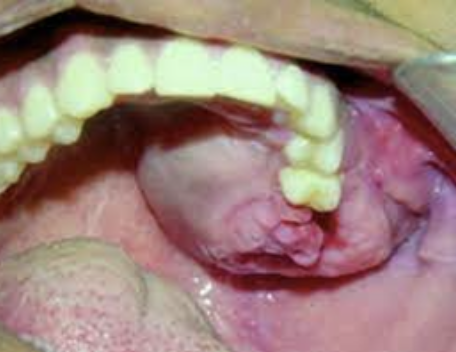

Wat is een pulpa poliep?

Een pulpa poliep of chronische hyper plastische pulpitis, is het gezwollen roze ontstoken weefsel dat te zien groeien is in de mondholte van een open ruimte aan de buitenzijde van de tand. Het is een aandoening die niet vaak voorkomt en dan uitsluitend bij kinderen en jonge volwassenen met sterk carieuze elementen waarbij een opening aanwezig is van de pulpakamer. Het granulatieweefsel in de pulpaholte woekert door de opening naar buiten waarna het geëpitheliailiseerd wordt. De patiënten hebben geen pijnklachten en manipulatie van de pulpa poliep is niet pijnlijk omdat het granulatieweefsel niet geïnnerveerd is. Manipulatie kan wel aanleiding geven tot een bloeding, omdat het granulatieweefsel doorgaans goed gevasculariseerd is. Een goede vascularisatie van de pulpa en een wijd foramen apicale gecombineerd met een grote weefselweerstand zijn noodzakelijk voor het ontstaan van een pulpapoliep.